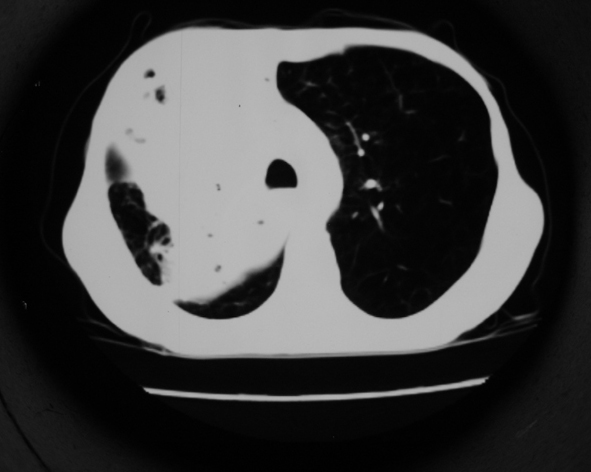

男53岁,咳嗽气短,以往身体健康.

右肺上叶多发多形态空洞及增殖灶,可见团块钙化,胸膜肥厚、粘连,考虑继发型肺结核可能性大

1.右肺上叶干酪性肺炎,2。肺气肿,肺大泡

支持右上肺继发性肺结核并干酪性肺炎,右肺大泡,左肺代偿性气肿。